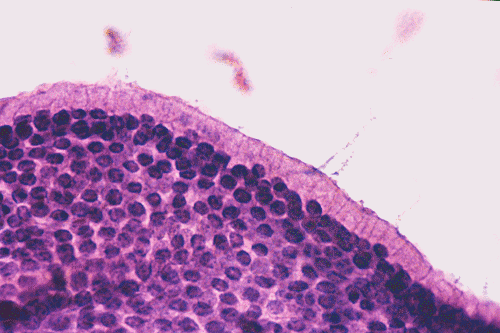

On low-magnification (Panel A),  the lesion contains has multiple glandular structures in a background of fibroconnective tissue. There is no inflammation. The epithelial component does not seem to have a complex architecture or papilla. On medium-magnification photographs (Panel B and C), the lining epithelium is low-columnar and single layered. Mucin secretion is noted on high-magnification photograph (Panel D). On intraoperative cytologic preparation (squash preparation), the single layer architecture of low-columnar cells is well appreciated (Panel E).